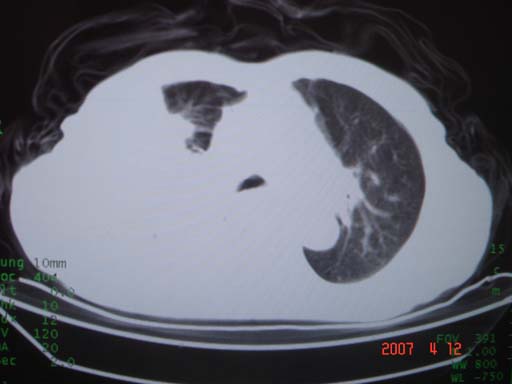

帮我 看看。男77岁咳嗽咯血2月发热2周!病人一般情况可 口痰为鲜红,有点象洗肉水(我看见他吐的痰了)

优先考虑右上肺干酪性肺炎并同侧中叶播散、胸腔积液。分析:右膈肌未见升高、纵隔未见明显右移,胸部各组淋巴结未见可疑肿大,中叶可见支气管铸形,肺野、肺门未见可确定肿块。

年龄偏大,应考虑右肺中央型肺癌并阻塞性肺炎 阻塞性肺不张,胸腔积液

考虑右侧中心型肺癌伴中叶肺不张,右侧 胸腔积液

右肺上叶中心型肺癌并上叶阻塞性肺炎,中叶炎症,右侧胸腔积液

右肺上叶后段支气管中断,首先考虑中央型肺癌并右肺不张及纵隔淋巴结转移,右侧胸腔积液。

有点象洗肉水的痰,其来源应当是实变引起的血细胞渗出导致,可见支气管气象,实变区有虫蚀状空洞,有明显胸腔积液,未见明显肺门区肿块影,考虑继发型肺结核,干酪性肺炎

右肺上叶实变,实变范围如此之大,如果用肺癌解释的化,应该是比较大的支气管开口发生完全阻塞,但观察上叶前后段支气管还是比较通畅,所以应考虑感染性病变,大叶性肺炎可能,建议抗炎治疗后复查。

肺癌肋骨转移